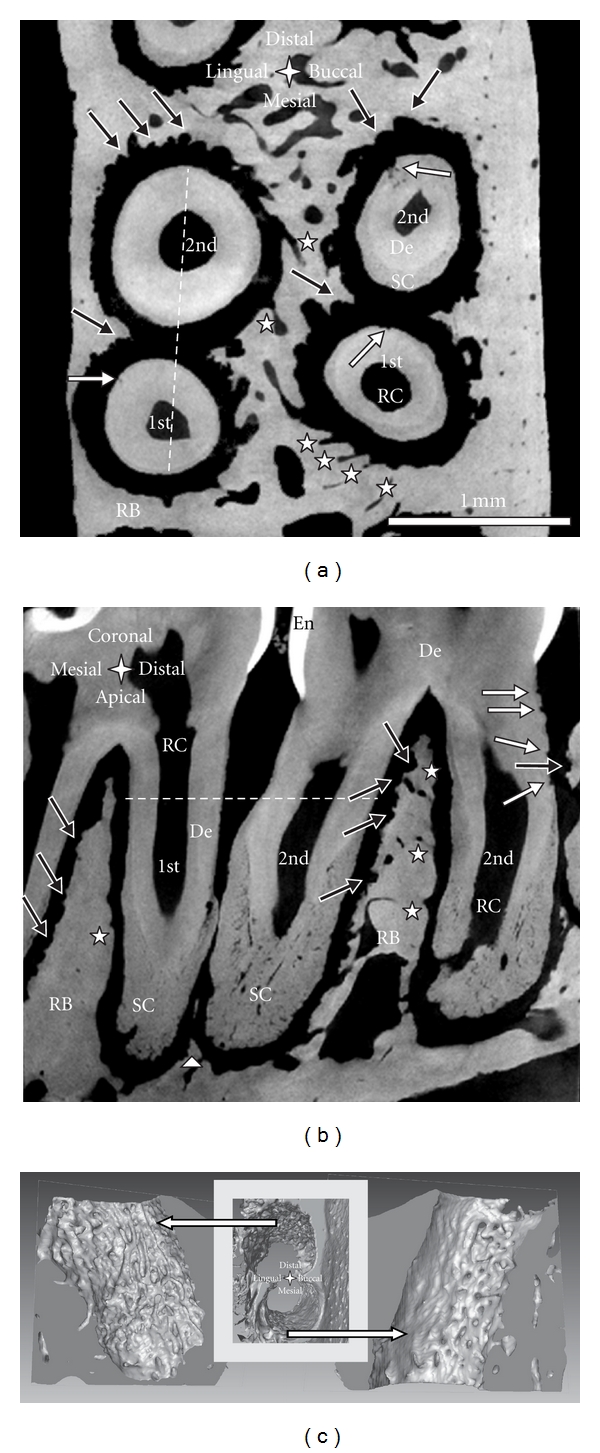

适应大鼠牙槽复合体是用各种成像方式说明。用于三维建模的微x射线计算机断层扫描,结合互补技术,包括图像处理、扫描电子显微镜、荧光标记、常规组织学(H&E、TRAP)和免疫组织化学(RANKL、OPN),阐明了大鼠牙周组织中骨、牙周韧带间隙和牙骨质的动态特性。断层扫描和电子显微镜以更高的分辨率显示钙化组织的结构适应。正在进行的生物矿化分析使用荧光标记,并通过评估衰减剖面从三维断层扫描的虚拟切片。通过结合组织学、免疫组织化学和断层扫描来说明破骨细胞分布作为解剖位置的功能。虽然断层扫描和扫描电镜提供了过去的吸收相关事件,但未来的适应性变化是通过免疫组织化学鉴定基质生物分子来推断的。因此,在大鼠牙槽嵴复合体的动态图片被说明。

Adaptation of a rat dentoalveolar complex was illustrated using various imaging modalities. Micro-X-ray computed tomography for 3D modeling, combined with complementary techniques, including image processing, scanning electron microscopy, fluorochrome labeling, conventional histology (H&E, TRAP), and immunohistochemistry (RANKL, OPN) elucidated the dynamic nature of bone, the periodontal ligament-space, and cementum in the rat periodontium. Tomography and electron microscopy illustrated structural adaptation of calcified tissues at a higher resolution. Ongoing biomineralization was analyzed using fluorochrome labeling, and by evaluating attenuation profiles using virtual sections from 3D tomographies. Osteoclastic distribution as a function of anatomical location was illustrated by combining histology, immunohistochemistry, and tomography. While tomography and SEM provided past resorption-related events, future adaptive changes were deduced by identifying matrix biomolecules using immunohistochemistry. Thus, a dynamic picture of the dentoalveolar complex in rats was illustrated.